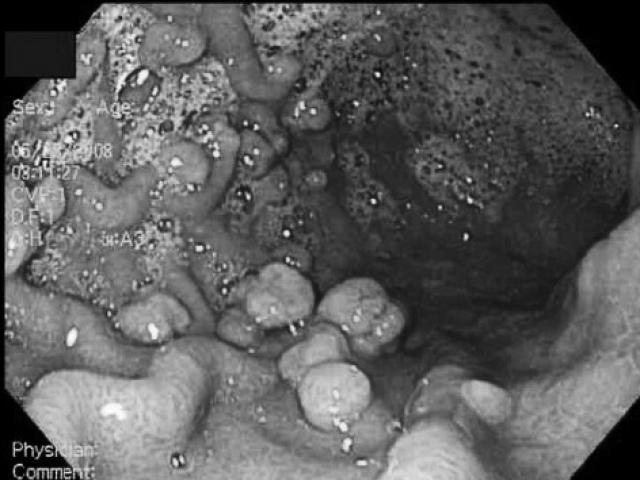

Tại BV, bác sĩ chẩn đoán người bệnh bị suy giãn tĩnh mạch hai chân độ 3, tĩnh mạch nông giãn nhiều, sưng chân, siêu âm tĩnh mạch.

Theo ThS BS. Trần Thanh Vỹ - Trưởng khoa Lồng ngực Mạch máu BV ĐHYD cho biết, suy giãn tĩnh mạch là tình trạng suy yếu chức năng dẫn máu trở về tim của hệ thống tĩnh mạch ở chân, gây ứ đọng máu ở vùng thấp của chân và lan lên dần. Hậu quả là gây ra các dấu hiệu như nặng mỏi chân, đau nhức bắp chân, vọp bẻ, nổi gân xanh (tĩnh mạch) ngoằn ngoèo, phù chân, ngứa da,…

Tình trạng ứ đọng này kéo dài qua nhiều tháng, nhiều năm và ngày càng nặng, gây ra nhiều biến chứng nguy hiểm, khó trị như loét chân, tắc mạch, viêm mạch,… nếu không được điều trị kịp thời, đúng cách.